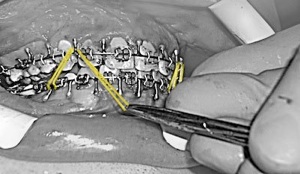

La technique chirurgicale a été décrite décrite par Perthes Schliessmann en 1932. Il s’agit de l’ostéotomie mandibulaire Haute, ou courte, ou sus-spigienne. La plus grande difficulté est technique, puisque l’ostéosynthèse est très haute. Le tournevis contre-angle de Fritzemeier permet de limiter la taille de l’incision. Cet instrument permet de réaliser une chirurgie mini-invasive.

Comment placer les élastiques?

Les premiers jours, les élastiques sont laissés en place, et l’alimentation est liquide

Dès le deuxième jour, il faudra apprendre à retirer les élastiques